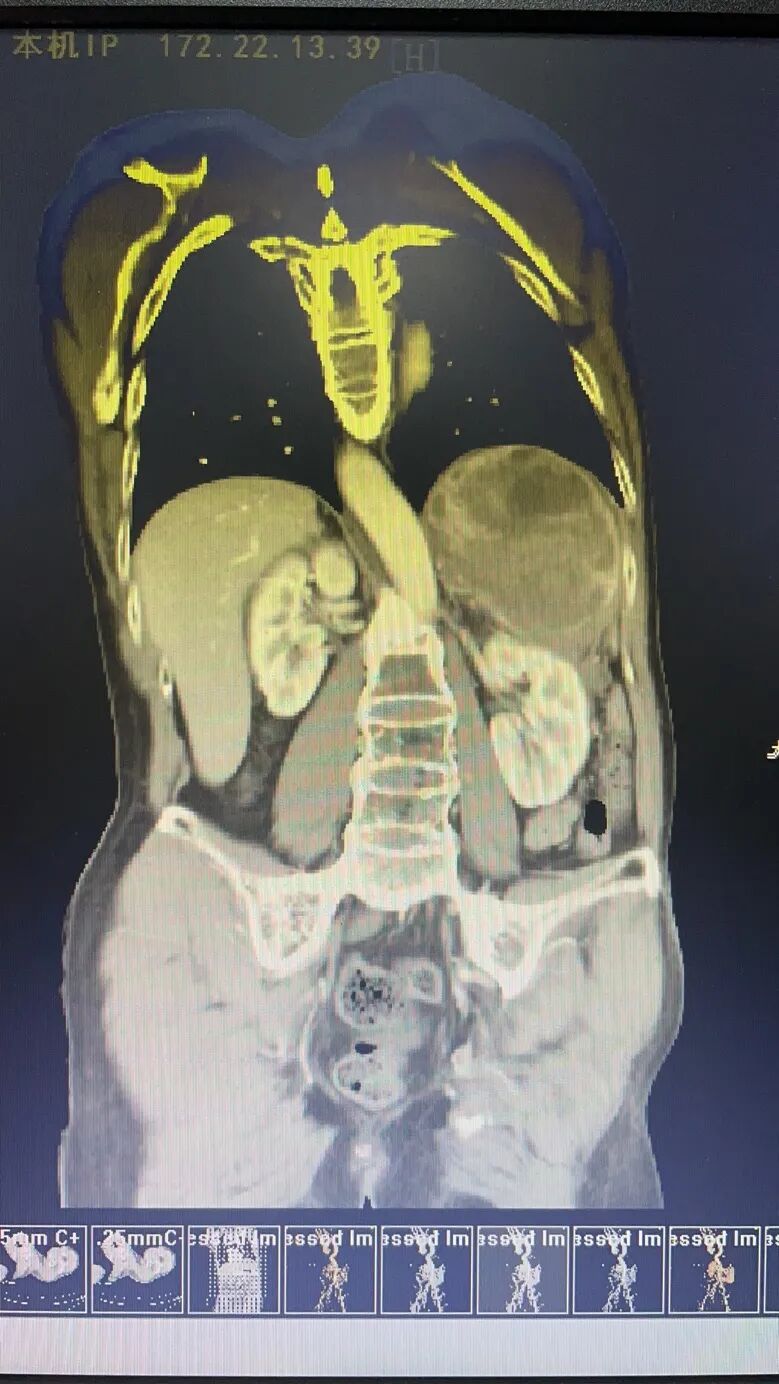

去年12月,56歲的張叔開始感到反復(fù)胸悶、左季肋區(qū)刺痛不適,特別是左上腹有種被壓迫的感覺,不管站著、坐著還是躺著都讓他十分難受,要將枕頭墊很高才能入睡。為此,張叔前來惠州三院急診科就診,測量血壓達到了200/115mmHg。急診科對張叔進行控制血壓治療,但張叔的血壓用普通的降壓藥根本無法控制,只好使用靜脈微泵注射降壓藥控制血壓。完善心肌梗塞、主動脈夾層等相關(guān)檢查未見明顯異常,發(fā)現(xiàn)CT顯示左側(cè)腹膜后有一個巨大腫瘤性占位,最大直徑達到16cm!為了進一步診治,張叔經(jīng)惠州三院泌尿外科會診后被收入了??撇^(qū)。

入院后,普泌腫瘤組組長田生平主任醫(yī)師立即指示管床醫(yī)生全面完善腎上腺腫瘤相關(guān)的術(shù)前檢查,以作出腎上腺腫瘤的定性、定位診斷及評估患者術(shù)前心肺功能。由于此類腫瘤手術(shù)風險極高,檢查結(jié)果出來后,田生平主任醫(yī)師立即請示泌尿外科科主任、學科帶頭人楊偉忠主任醫(yī)師,并在其指導下,針對張叔的診斷、治療方案先后進行了多次全科討論以及院內(nèi)多學科會診,最終診斷高度懷疑左側(cè)腎上腺巨大嗜鉻細胞瘤(唯一的確診方式是手術(shù)切除后送病理科診斷)。針對嗜鉻細胞瘤,根治辦法就是手術(shù)切除,但由于嗜鉻細胞瘤的手術(shù)風險極高,且張叔體內(nèi)的巨大嗜鉻細胞瘤瘤體血液供應(yīng)十分豐富,患者手術(shù)過程中極易出現(xiàn)難以控制的高血壓、難以恢復(fù)的低血壓以及大出血的風險!

手術(shù)于3月24日上午進行,由中山大學附屬腫瘤醫(yī)院泌尿腫瘤科董培教授作主要技術(shù)指導,惠州三院泌尿外科科主任楊偉忠主任醫(yī)師、麻醉科科主任龍宏杰主任醫(yī)師、手術(shù)室護士長梁雪景副主任護師親自坐鎮(zhèn),為患者在手術(shù)過程中的心率、血壓等重要生命體征保駕護航。開刀后,患者張叔的巨大嗜鉻細胞瘤及周邊豐富、粗大的營養(yǎng)血管暴露在大家眼前,損傷后極易出血,必須逐一結(jié)扎后才能推進腫瘤切除。然而,由于腫瘤實在太大了,嚴重遮擋視野,出血難以避免,止血十分困難,長時間壓迫止血還會導致血壓受刺激升高,情況危急!教授眼疾手快,果斷先壓迫止血,在血壓升高前爭分奪秒切除腫瘤,以最快速度結(jié)束戰(zhàn)斗!